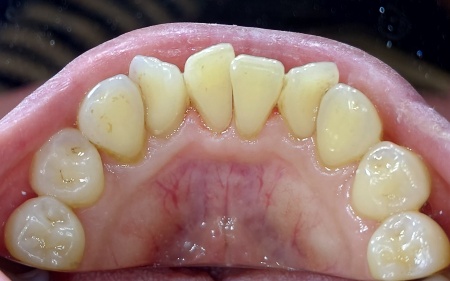

30代女性 重度の歯周病に対して歯周内科治療を行った症例

- 歯石除去

- 歯周病

- 治療期間の目安 -

-

治療回数の目安

2回

※保険診療回数・ブリッジ治療は含まれない -

治療費総額の目安

55,000円(歯周内科治療)

※保険治療費・ブリッジ治療費は含まれない